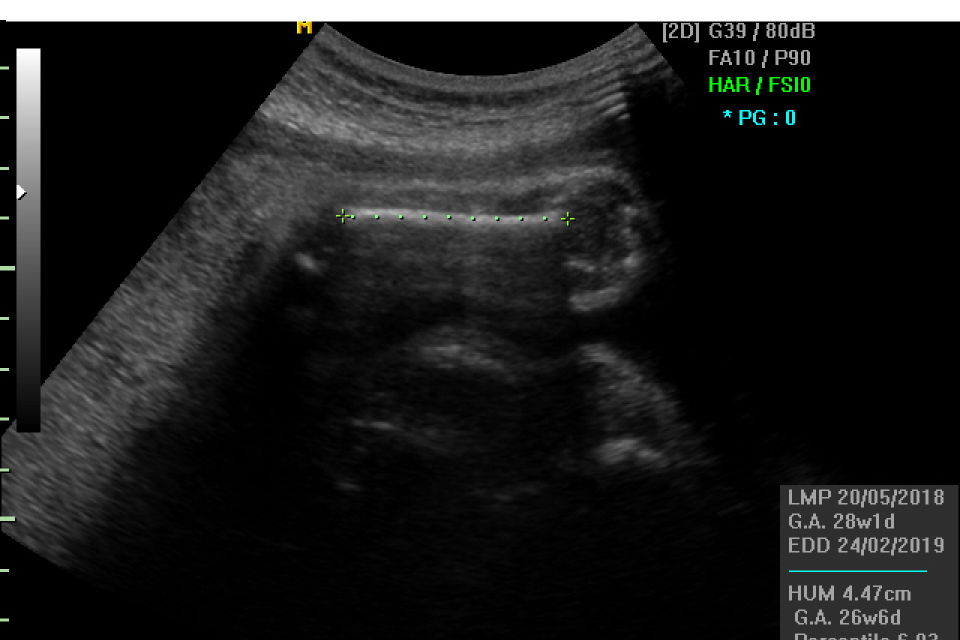

E` una ecografia che valuta principalmente la crescita del bambino, lo stato della placenta, la quantita` di liquido amniotico. Nel corso dell`esame vengono misurati la circonferenza cranica, la circonferenza addominale, il diametro della testa e la lunghezza del femore per poter stimare il peso fetale. Si controlla anche lo stato di benessere degli organi fetale per valutare che la loro formazione segua un decorso regolare rispetto al controllo effettuato durante l`ecografia morfologica. Vengono anche rilevati i movimenti del bambino sia respiratori che del corpo, che insieme alla valutazione del liquido amniotico costituiscono il profilo biofisico fetale, espressione dello stato di benessere del bambino.

E` una ecografia condotta principalmente per via addominale sempre utilizzando del gel. Viene eseguita fra la 28 e la 33 settimana di gestazione.